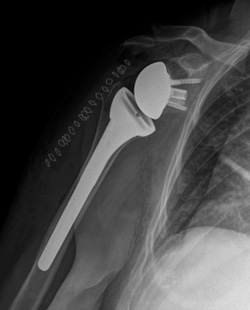

Anatomisk skulderprotese

Den anatomiske skulderprotese ligner en almindelig skulders anatomi. Den består af en ledskål, der er lavet af et meget holdbart plastik materiale (polyethylen) og et ledhoved, som er lavet af rustfrit stål. Protesedelene kan forankres til knoglen på forskellige måder, og metoden vælges ud fra forskellige parametre, som kirurgen vurderer under operationen. En anatomisk protese kan kun bruges, hvis alle styresenerne er normale.

Røntgenbillede af anatomisk skulderprotese

Røntgenbillede af anatomisk skulderprotese, der viser ledhovedet, der er forankret ned i knoglen på overarmen. Ledskålen er lavet af plastik og ses derfor ikke på røntgen, fraset en lille clips, der er indlejret i plastikken.